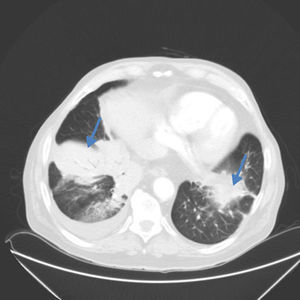

La TC torácica visualizó un infiltrado alveolar de límites mal definidos, con aspecto de masa polilobulada en el segmento anterior del lóbulo inferior derecho y un nódulo sólido en el mismo lóbulo de 25mm de diámetro en relación con un derrame pleural. Además presentaba infiltrados parcheados con áreas en vidrio deslustrado en língula y lóbulo inferior izquierdo (fig. 1).

Recientemente Huo et al., han descrito la presencia de granulomas de células epitelioides o células gigantes multinucleadas en resecciones de neumonías organizadas focales relacionando su origen a una etiología infecciosa4,5. En el paciente no existía historia de exposición compatible con una neumonitis por hipersensibilidad. Por el contrario, la presencia de una condensación con broncograma aéreo, un nódulo e infiltrados parcheados con múltiples áreas en vidrio deslustrado son hallazgos habituales en la neumonía organizada, y aunque no se pudo descartar la etiología infecciosa existen series en las que la neumonía organizada asocia derrame pleural hasta en el 20% de los pacientes con lesiones focales.